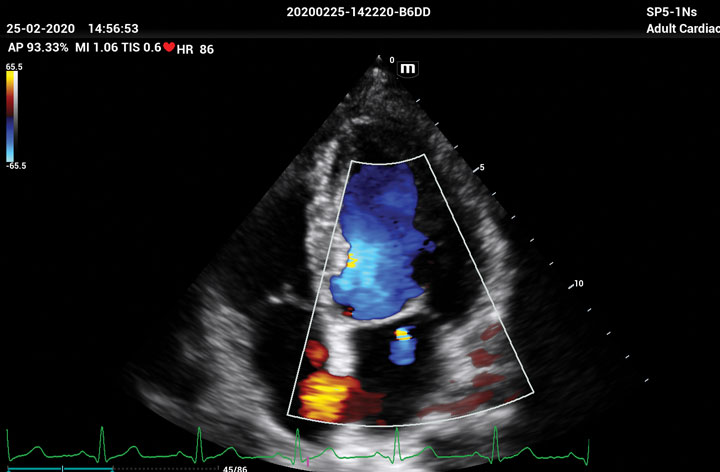

The ME8 Ultrasound System has been thoughtfully designed to overcome the obstacles clinicians face in today’s challenging healthcare environment. Powered by our groundbreaking software-based beamformer technology, ZONE Sonography® Technology+(ZST+), the ME8 Ultrasound System empowers decision-making by providing end-users best-in-class image quality and access to a comprehensive suite of workflow enhancement tools.